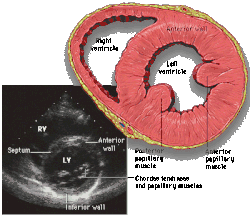

![]() Subcostal four chamber | ![]() Apical four chamber | ![]() Parasternal long axis | ![]() Parasternal short axis | ||||||||

| Each figure contains a TTE with a black background, and a corresponding colored illustration. | Patrick J. Lynch and C. Carl Jaffe, Yale University, 2006. | ||||||||||

| Click on a figure to enlarge it and see some parts of the heart identified. RV, right ventricle; LV, left ventricle; RA, right atrium; LA, left atrium; TV, tricuspid valve; MV, mitral valve; AV, aortic valve; RVOT, right ventricular outflow tract; LVOT, left ventricular outflow tract | |||||||||||